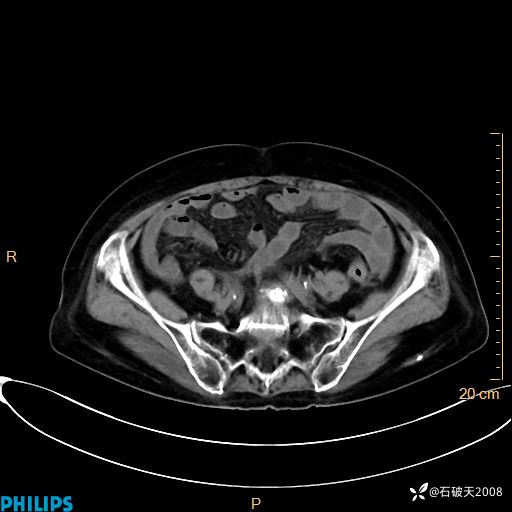

MIP